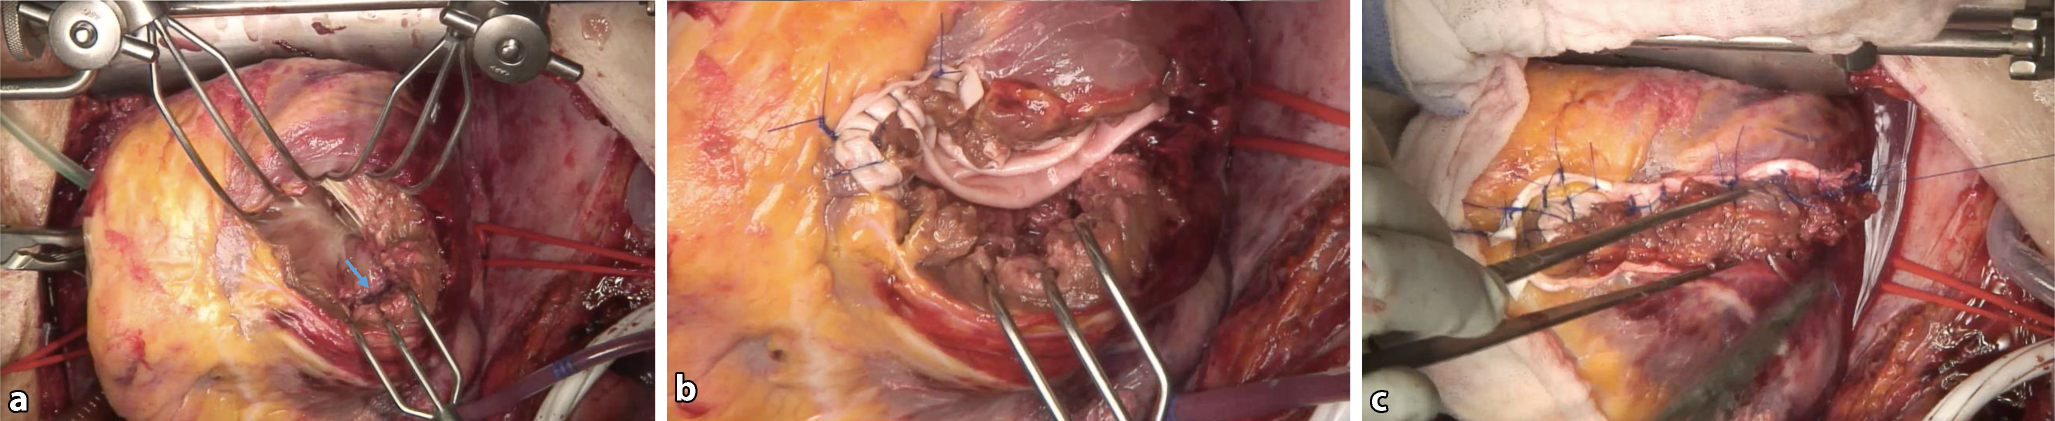

Abb. 1

Intraoperativer Situs bei Papillarmuskelruptur mit akuter hochgradiger Mitralinsuffizienz. a Der Patient ist an der Herz-Lungen-Maschine. Der Zugangsweg ist eine Sternotomie. Der linke Vorhof ist eröffnet und in der Pinzette wird der abgerissene Papillarmuskelteil gehalten (blauer Pfeil). Dadurch kommt es zum Prolaps großer Anteile der Mitralsegel. b Operationspräparat mit abgerissenem Papillarmuskelanteil und daran hängenden Sehnenfäden und (exzidierten) Mitralsegelteilen